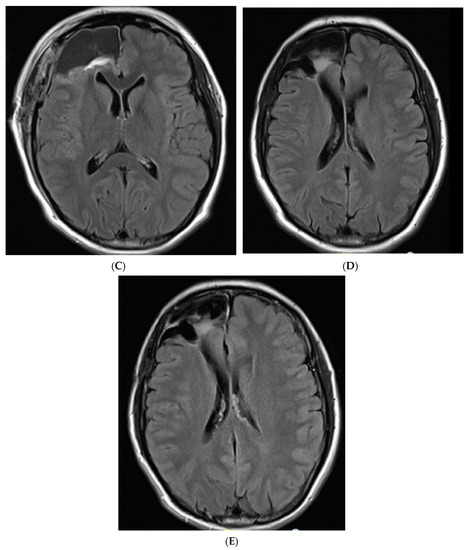

2. Case Description